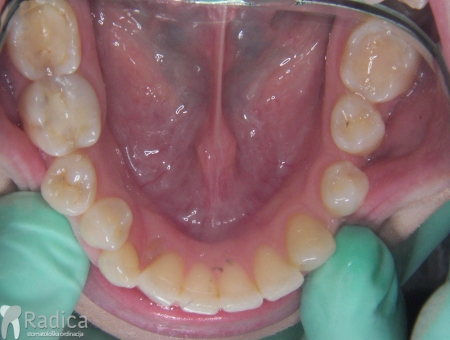

U ovom slučaju je 41.godinu starom pacijentu počeo nicati impaktirani desni gornji očnjak pri čemu je ugrozio lateralni sjekutić. Pacijentu je stavljen fiksni aparat te je zub smješten u luk. Kako je pacijent odustao od postave aparata u donjoj čeljusti na kraju nije dobivena zadovoljavajuća okluzija na što je upozoren.

U ovom slućaju 28 godina star pacijent je zatražio ortodontsku terapiju. Na pregledu je uočen perzistentni donji desni mliječni očnjak a ortopan je potvrdio postojanje impaktiranog trajnog nasljednika. Tijekom terapije je uočeno oštećenje korijena desnog lateralnog sjekutića koji je izvađen a na njegovo mjesto je postavljne očnjak i preoblikovan ljuskicom.

U sljedećem primjeru prikazan je pacijent kojemu je očnjak niknuo na nepcu i pomoću aparata smo ga smjestili u zubni luk.